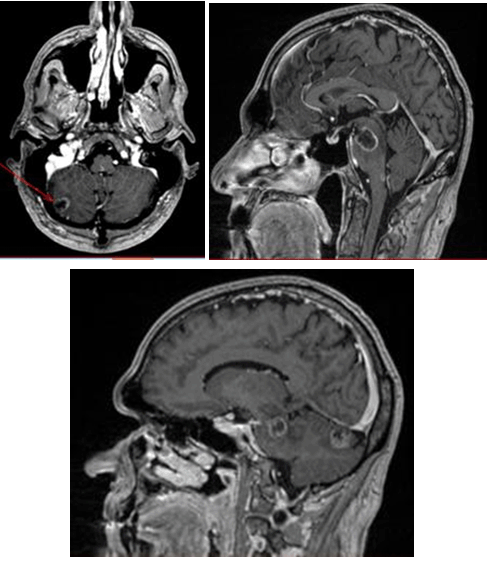

Five months later, an additional lung mass was discovered, and the patient received chemotherapy with FOLFIRI (Leucovorin calcium, fluorouracil and irinotecan hydrochloride) for four cycles. After four cycles, the lung tumor became radiographically occult. At the time of the lung tumor treatment, a blood sample was sent for multi-gene sequencing of circulating tumor DNA. A loss of function mutation in TP53 (M237I) was found along with an activating mutation in PDGFRA (L1000V). Unfortunately, targeted clinical trials were unavailable within the patient's travel area at that time, so he pursued observation only. Five months later, the patient started complaining of left ear and face paresthesia. A brain MRI in November 2015 revealed ring enhancing lesions in the medulla, right frontal lobe, right cerebellum (two lesions) and a lesion involving the pons and midbrain. The brainstem lesion was the largest lesion measuring 22x22x19 mm (Figure 1).

Cursor on image to zoom/Click text to open image

Figure 1: Magnetic resonance images of metastatic lesions in the brainstem and cerebellum. Image (A) is a sagittal T1 post gadolinium sequence demonstrating a 2.3 cm rim enhancing lesion in the pons and mid-brain. Image (B) is an axial T1 post gadolinium sequence showing a 1.3 cm rim enhancing lesion of the cerebellum. Image (C) is an sagittal T1 post gadolinium sequence of an additional cerebellar lesion and a portion of the mid-brain lesion.